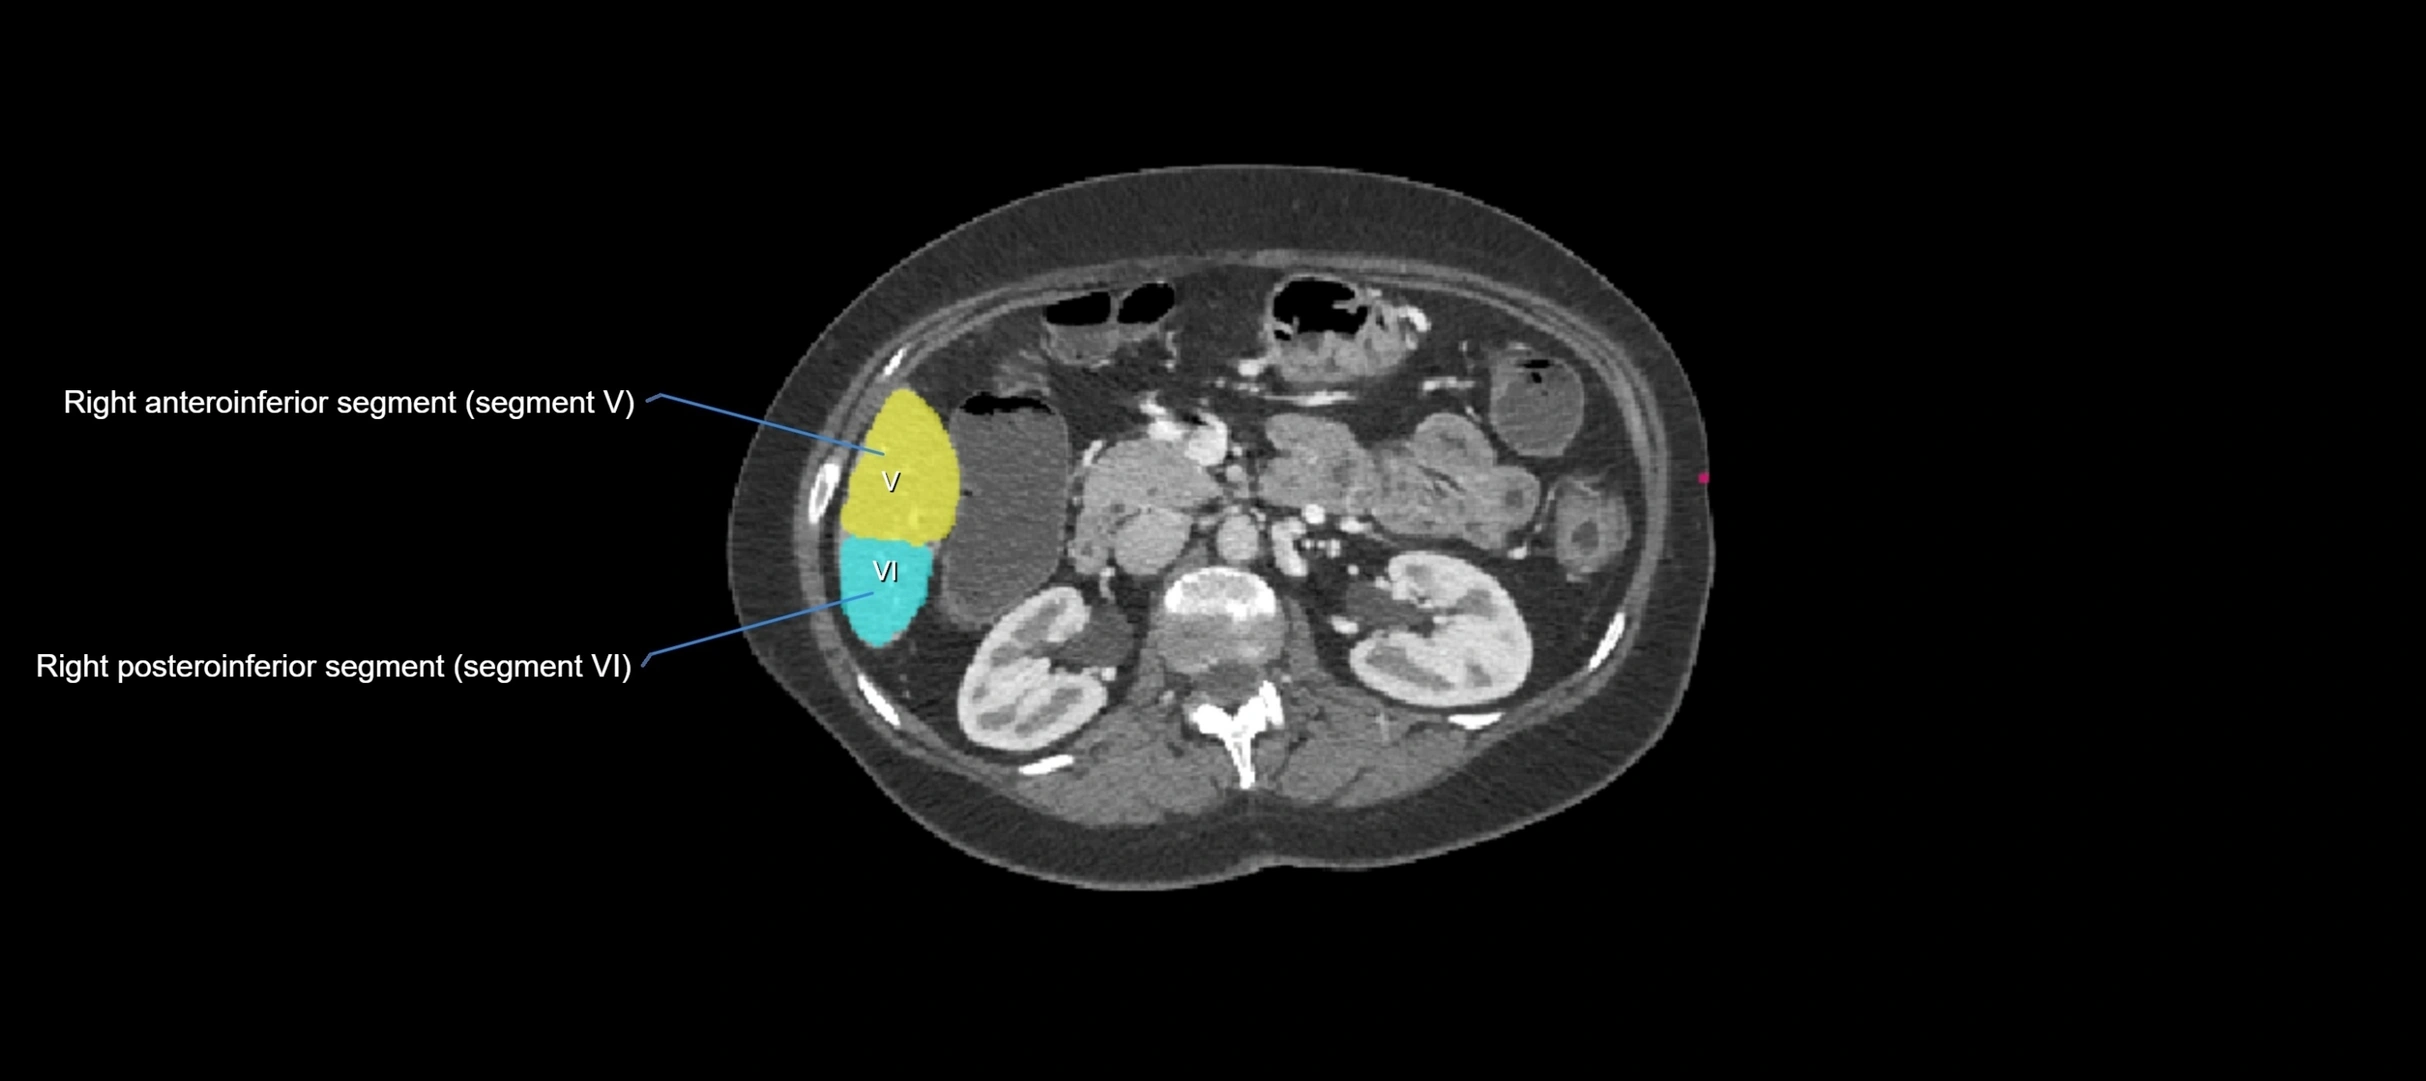

CT Image

image